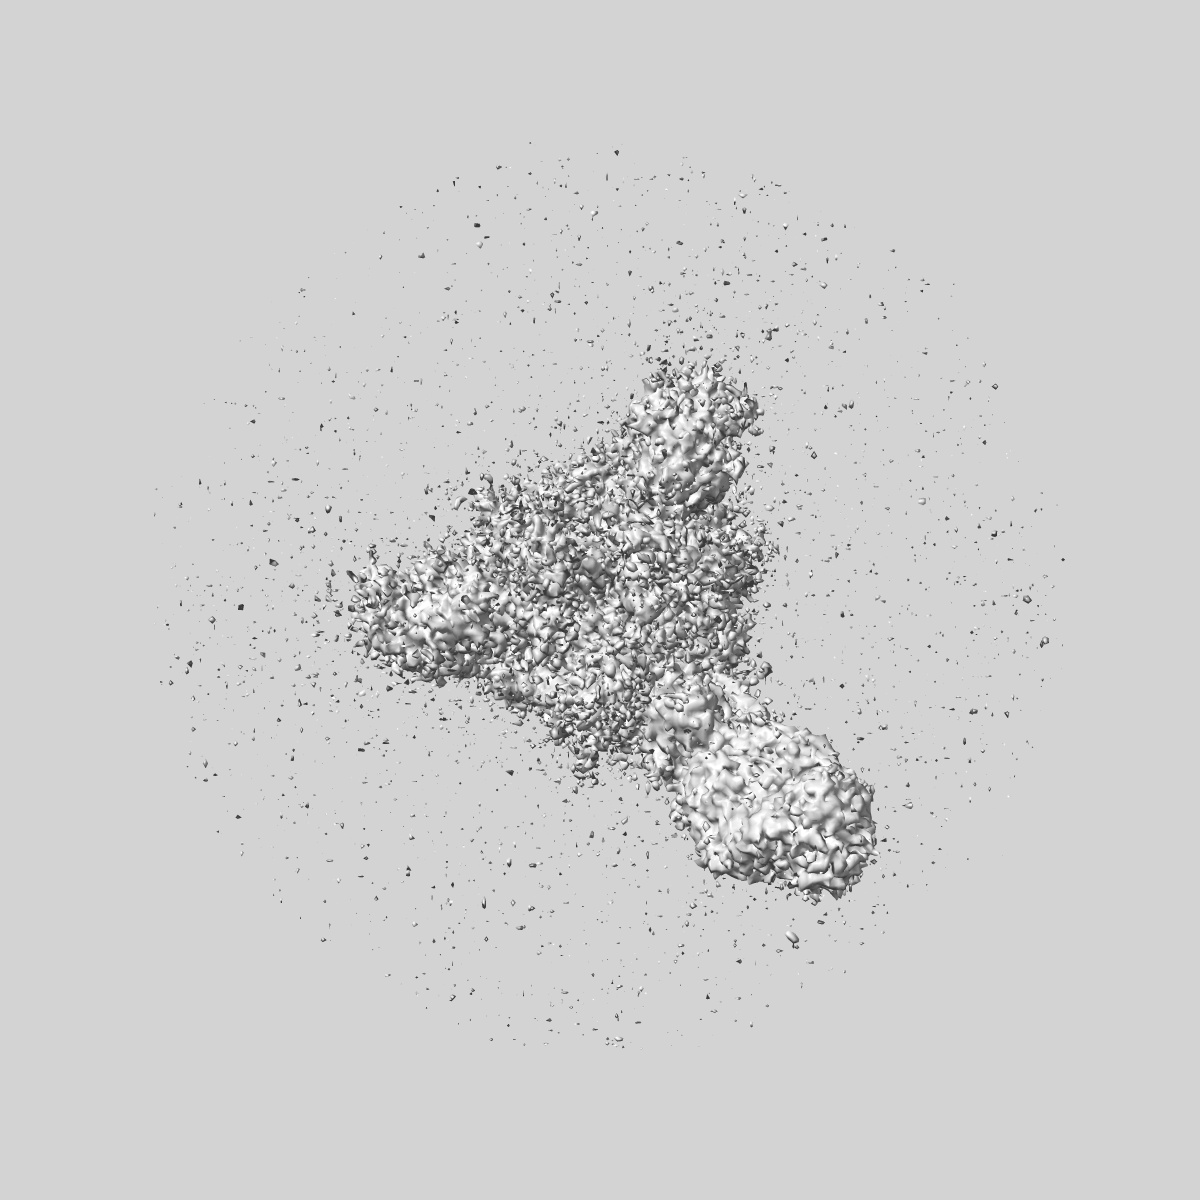

SARS-CoV-2 Wuhan Spike ectodomain in complex with human polyclonal antibody ModWu-NTD1 (mRNA-1273 vaccine)

Single-particle3.4 Å

Sample: SARS-CoV-2 Wuhan spike ectodomain in complex with human polyclonal antibody ModWu-NTD1